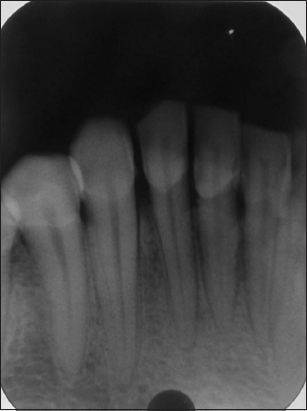

On the basis of history and clinical findings, a provisional diagnosis of irritation fibroma was given. The list of differential diagnosis included chronic fibrous epulis, peripheral giant cell granuloma, osteosarcoma, chondrosarcoma, pyogenic granuloma, and peripheral odontogenic fibroma. The investigations included complete hemogram, intraoral radiographs, and excisional biopsy of the lesion. Routine hematological investigation values were also found to be within normal limits. No radiographical changes related to the bone were seen [Figure 2]. As the patient reported discomfort during eating and while speaking, it was decided to go for an excisional biopsy performed under local anesthesia using a scalpel [Figure 3]. The excised tissue [Figure 4] was sent to the department of oral pathology for histopathological examination and H and E stained section revealed parakeratinized stratified squamous epithelium with elongated rete ridges. Irregular multiple foci of homogenous calcified areas were evident within the connective tissue. Thus, a final diagnosis of irritation fibroma was given [Figure 5]. Patient was recalled after 1 week for revaluation which shows satisfactorily healing and patient was asked to maintain oral hygiene [Figure 6]. No recurrence of fibroma was seen when patient was recalled after 6 months for follow-up [Figure 7].

Figure 2: IOPA irt 31, 32, 33, 41, and 42